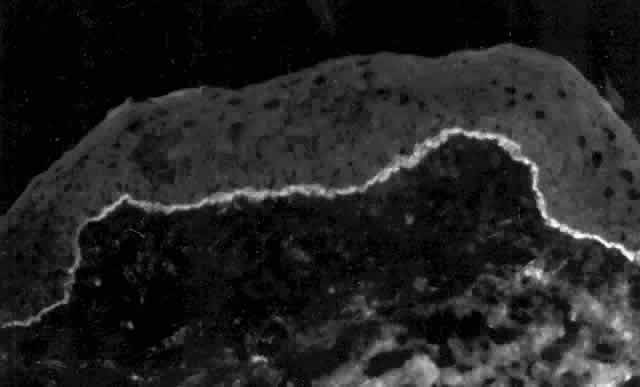

Clinically, the ocular disease in cicatricial pemphigoid (OCP) may present unilaterally in the form of a chronic, recurrent catarrhal conjunctivitis, but it eventually becomes bilateral. Subepithelial fibrosis is characteristic of stage 1 of OCP (Fig. 7). Stage 2 shows fornix foreshortening (Fig. 8), and symblepharon formation is the hallmark of stage 3 (Fig. 9). Stage 4, end-stage disease, is characterized by ankyloblepharon and surface keratinization (Fig. 10). Obstruction of the lacrimal ductules and meibomian gland ducts eventually produces an unstable tear film and progressive sicca syndrome, but it is to be emphasized that OCP is not a dry-eye syndrome until late in the disease course.20 Trichiasis and entropion occur because of the subepithelial fibrosis, with eventual keratopathy, corneal neovascularization, and corneal ulceration and scarring.20

Fig. 7. Stage 1 cicatricial pemphigoid, with cicatrizing conjunctivitis, and fine striae-type areas of subepithelial fibrosis, but without evidence of shrinkage of the conjunctiva.